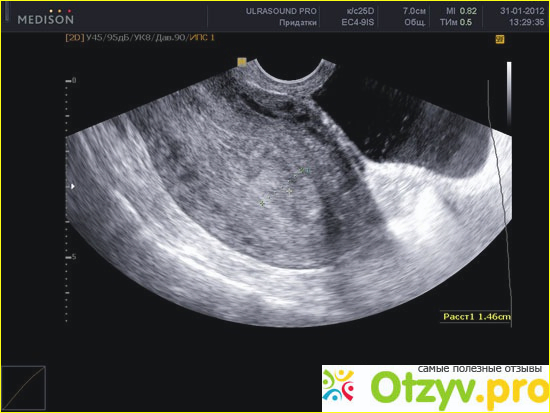

УЗИ матки как метод исследовния

Проведение процедуры обследования

При проведении обследования можно в данном случае получить много полезной и ценной информации, - в частности выявить спаечный процесс, который является результатом протекающего воспаления. Также легко при этом в большинстве случаев выявить пороки, из-за которых становится невозможным зачатие ребенка. При помощи УЗИ также определяется состояние матки, ее форма и как она расположена. Процедуру можно проводить по разным методикам и как она будет проводиться зависит от решения гинеколога – в зависимости от того, что нужно обследовать. Очень популярно применение трансвагинального метода связанного с применением специального датчика, который вводят через влагалище. При этом происходит максимальное приближение к органу, что позволяет получить максимально достоверную информацию. При трансабдоминальном методе исследование провидится через переднюю брюшную стенку. При этом, как было сказано выше, мочевой пузырь должен быть наполнен.